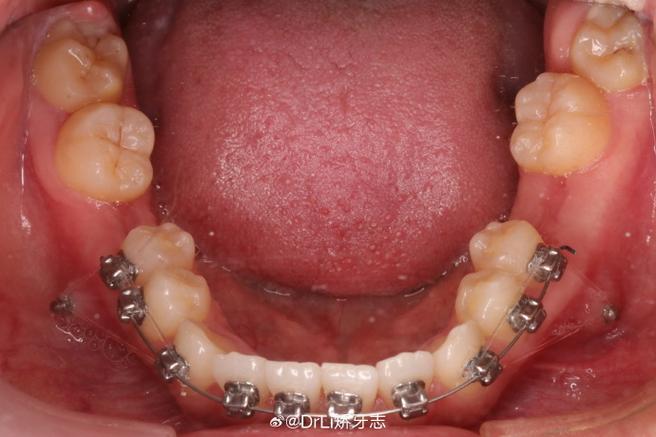

- 托槽粘接:演示托槽定位的关键标志点(如上颌中切牙切缘中点、下颌第一磨牙颊面管中心),结合口内视频展示酸蚀、涂粘接剂、放置托槽的细节,强调定位精度对矫治效果的影响。

- 弓丝更换与调整:从初始的镍钛圆丝开始,逐步展示更换为方丝、添加转矩、关闭间隙等操作,重点讲解弓丝入槽后的牙齿移动规律,如“滑动法关闭间隙”的力学原理。